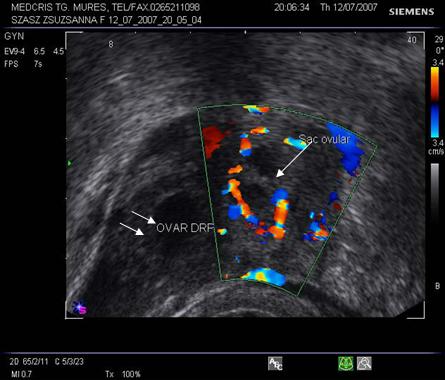

Fig nr58

Sac ovular intratubar ampular ( dg. complet doar laparoscopic, aici cu sageata ) cu imagine

caracteristica de coroana trofoblastica bine vascularizata la exam doppler

color . Alaturi se remarca ovarul drept cu corp galben, tot cu ecou hipoecogen

central ( marcat cu doua sageti )

Fig nr 59 Aceeasi sarcina ca in figura precedenta, in sacul ovular marcat cu o linie, se distinge clar sacul lui Yolk, alaturi de corpul galben ovarian drept